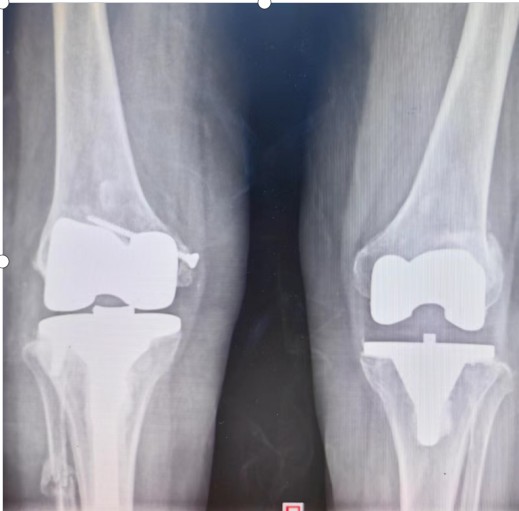

入院后羅湘平主任醫(yī)師、彭健副主任醫(yī)生及蔣瀟純主治醫(yī)師查體時發(fā)現(xiàn)劉奶奶的右膝關節(jié)重度外翻,內(nèi)側(cè)副韌帶松弛嚴重致膝關節(jié)失去穩(wěn)定性。CT檢查發(fā)現(xiàn)右膝關節(jié)外側(cè)脛骨平臺缺損明顯,深度達1.5厘米以上,長期應力異常,導致腓骨近端應力性骨折。這種復雜膝關節(jié)畸形行人工膝關節(jié)置換不但技術難度大,而且費用很高。根據(jù)劉奶奶膝關節(jié)評估結果,可能需要行鉸鏈膝關節(jié)假體及金屬墊塊充填骨缺損,僅假體材料費用就要達6萬余元,普通家庭無法承受。

羅湘平主任醫(yī)師團隊考慮患者的家庭經(jīng)濟狀況,決定力爭修復患者原有的解剖結構,避免使用更多的人工替代品,以減少患者的經(jīng)濟負擔。為了能夠順利完成手術、達到滿意的效果,羅湘平主任醫(yī)師做好充分的術前準備工作,精心設計手術方案,選擇為患者實施普通的人工膝關節(jié)置換,內(nèi)側(cè)副韌帶止點采用螺絲重建術恢復膝關節(jié)穩(wěn)定性,脛骨外側(cè)平臺骨缺損采用螺絲釘加骨髓泥充填,為患者節(jié)省3萬余元材料費。劉奶奶的膝關節(jié)畸形得到矯正、恢復了穩(wěn)定性,于術后第10天順利出院。

術前

術后